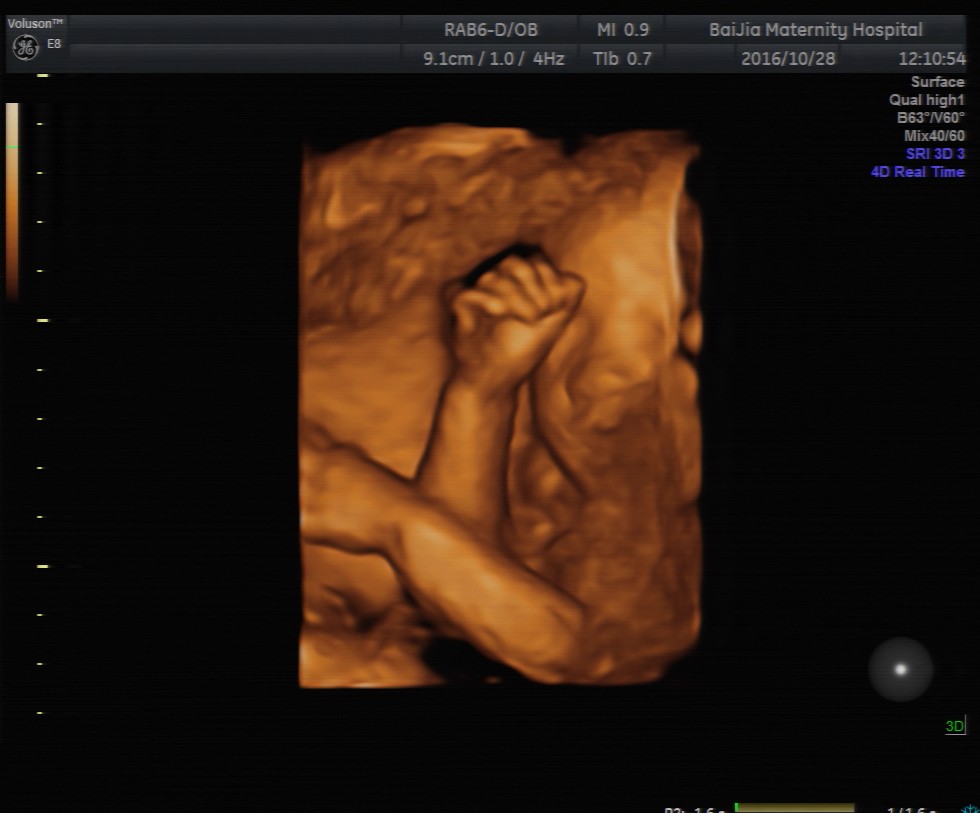

第一种:四维彩超是利用超声仪器中的软件将二维的平面图像模拟转换成动态、立体四维图像,有利于医生判断宝宝的发育情况是否正常以及是否存在重大畸形。检查时胎宝胎动比较频繁、表情动作也较多,像打哈欠、吸吮手指、吞咽口水等等,这些画面通过超声仪器呈现出来可能并不是那么好看。